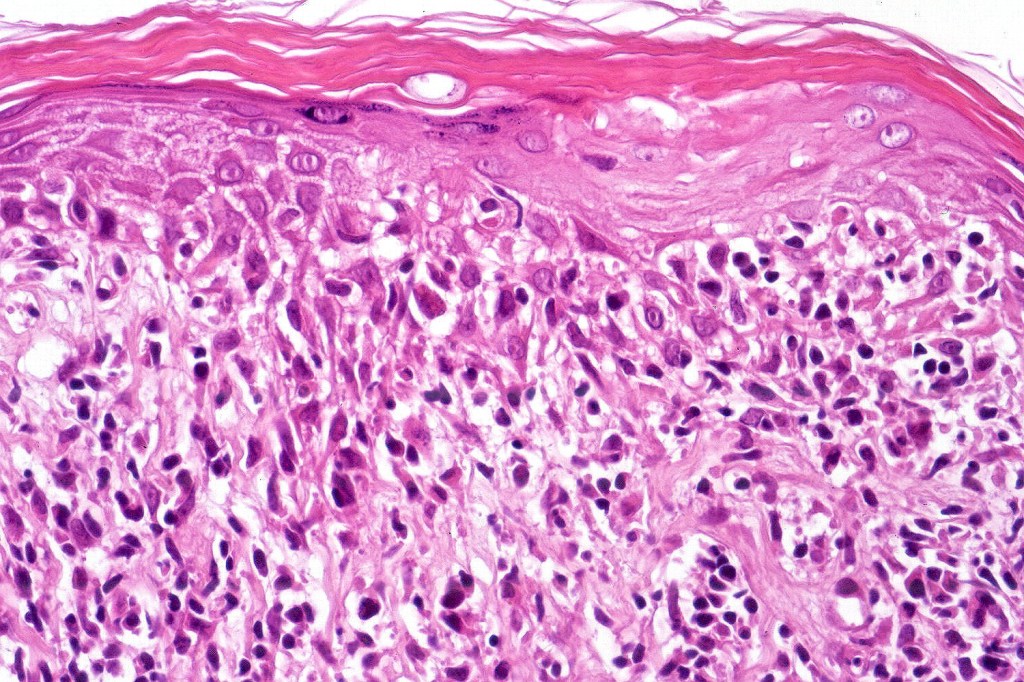

Histological features

The histological hallmark of mycosis fungoides is the presence of large atypical lymphocytes with a convoluted/cerebriform nuclear border (Sézary cells). These may be found at the epidermal-dermal jnuction and as collections within the epidermis (Pautrier microabscess). These are most easily found in plaque stage disease. The epidermal component can be subtle in patch stage disease and is often lost in tumor stage dsease. The classification into patch, plaque & tumor stage disease is less helpful histologically as the features merge from one to the other. It is all a matter of degree.

Plaque Stage Disease

•Compact hyperkeratosis & patchy parakeratosis

•Acanthosis

•Psoriasiform hyperplasia common

•Epidermotropism is often marked with conspicuous Pautrier microabscesses

•Lichenoid variant & poikiloderma atrophicans vasculare

•Variable folliculotropism (+/- mucinosis) & syringotropism

•Coarse collagen bundles in papillary dermis

•Superficial band-like dermal infiltrate of atypical lymphocytes, eosinophils, plasma cells & histiocytes